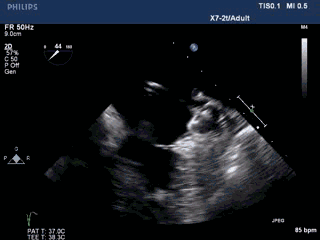

术前准备——TEE评价左心耳结构

左心耳呈多分叶状,口部梳状肌发达。